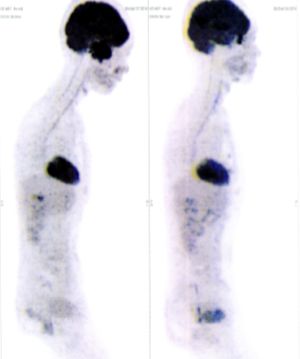

Below are some of the cases, from more than 80 cases we have treated so far with good results. When reading the PET/CT scans, the picture on the left is before treatment, and the picture on the right is after treatment. The intensity of black represents the activity of the cancer, but some black areas are not cancer: brain, heart, radioactive urine in bladder. For the heart, the intensity of black depends on the number of hours of fasting: if more than 10 hours, the heart is not even black, but if fasting is less than 6 hours, it is very black. The intensity of black in the brain can be variable in different scans depending on the brain activity at the time of the scan. The intensity of black in the radioactive urine can also be variable due to the hydration of patients and the time of injection of diuretic.

CASE NO: 1

(HEPATOCELLULAR CARCINOMA + STOMACH CANCER)

A middle-aged women who is very thin and very weak, can hardly walk, lying in bed most of the time. She saw a cancer specialist in a top hospital who discovered that she had massive hepatocellular carcinoma, and another cancer in the stomach. Given that hepatocellular carcinoma is incurable and stomach cancer is very difficult if not impossible to cure without surgery, she was told that nothing could be done for her. She came to ask us to help her. After just 4 treatment, the hepatocellular carcinoma went into remission, and the stomach cancer (arrow) became less active. Until today, more than 6 months later, the hepatocellular carcinoma is still in remission.